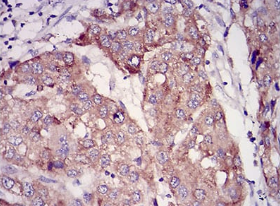

RAB27A Mouse Monoclonal antibody[7D7C9]

IHC    1/200 - 1/1000